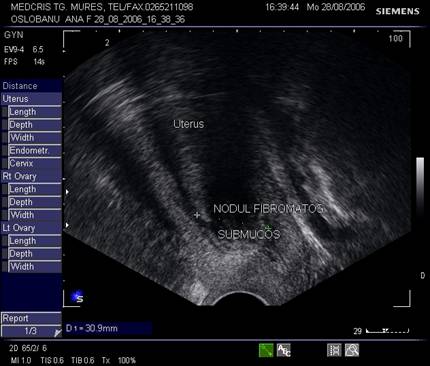

Fibromul uterin - cea mai frecvent intalnita tumora genitala, cu frecventa de 20 - 50% din femei [3].

Aproximativ 90% din fibroame (leiomioame) apar la nivelul corpului uterin. Se descriu, faza miomatozei difuze, fibroame intramurale, subseroase, submucoase, intraligamentare.Mioamele prezinta margini bine delimitate fata de miometru la ecografie, continand arii de mai mare sau mai mica ecogenitate in functie de modificarile degenerative.[1,6]

Fig. nr.385. Nodul submucos ce deformeaza cavitatea uterina, ecografie transvaginala